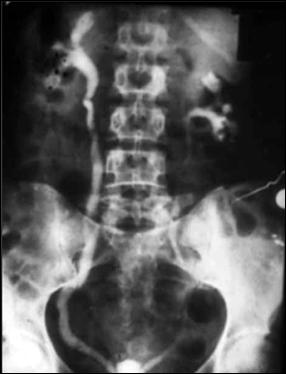

Diagnosticul diferential cu tuberculoza urogenitala

Vezica urinara are contururi greu delimitabile pe cistografie si pacientul are ureterohidronefroza bilaterala.

Figura 57. Vezica urinara mica |

Vezica urinara mica, scleroasa, cu rinichi drept unic chirurgical, uretero-hidronefroza gr I